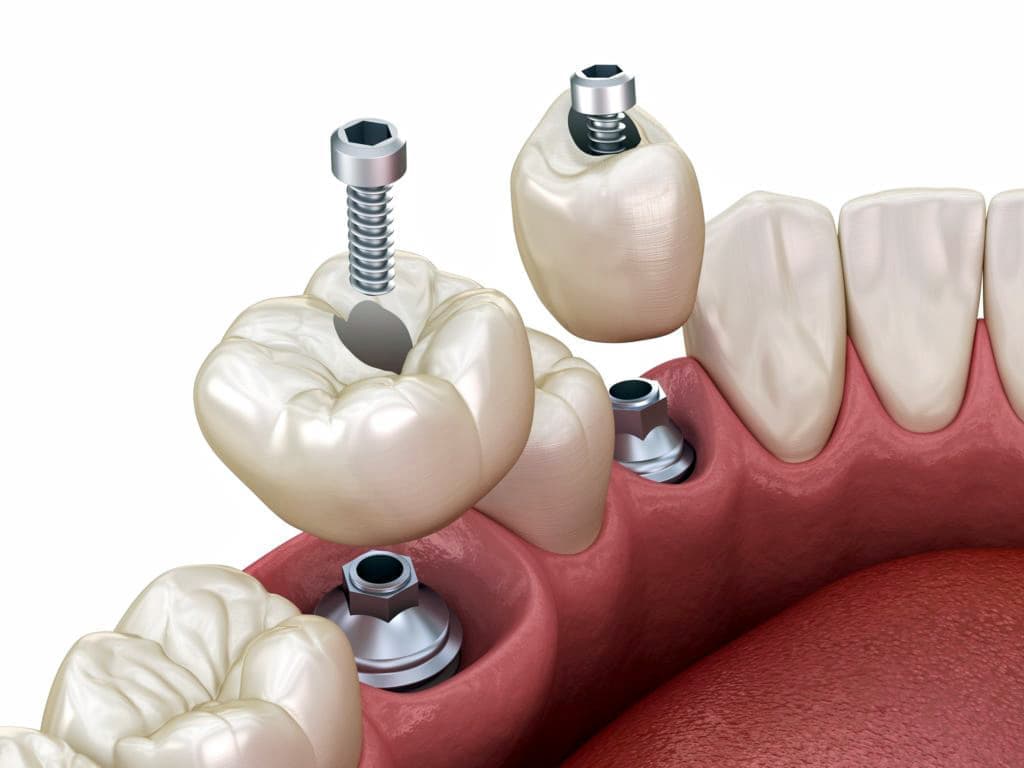

インプラントとは、顎の骨に人工歯根となる金属を埋め込み、その金属を土台にして、天然の歯と同じような人工の歯を取り付ける治療方法です。

埋め込む金属に生体との親和性が高いチタンが使われる事が多く、チタンは長年の臨床研究でインプラントの素材として最も安全であり、また顎の骨としっかり結合することが確認されています。

天然歯のような見栄えだけでなく、これまでの入れ歯やブリッジでは満足することが難しかった「食べる・話す」という機能も回復できます。

インプラントは周りの歯を傷つけず、残った歯への影響が少ないため、自分の歯を多く残せます。

また顎の骨がやせるのを防げる効果もあります。

食べ物のカスが挟まったり、留め金が見えるといったこともないので、衛生面や見た目からも、天然歯自分の歯と同じようにきれいで美しい状態を保てます。